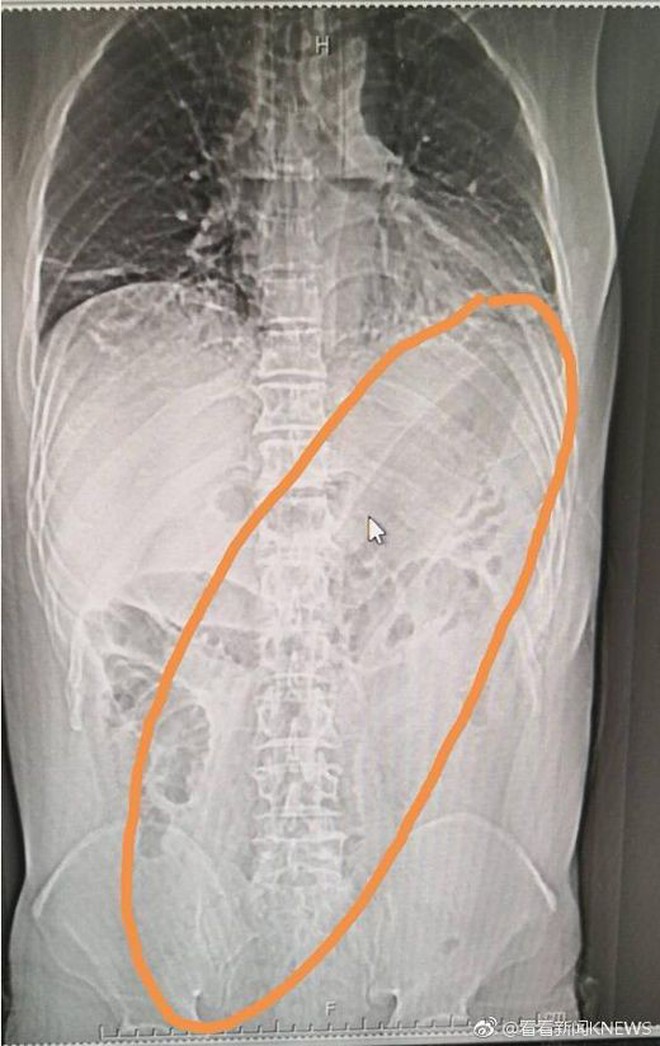

Hình ảnh chụp ích quang vị trí quả cả tím trong cơ thể người đàn ông.

Tại bệnh viện, hình ảnh X-quang cho thấy quả cà tím khổng lồ được đẩy vào mông người đàn ông đã gây ảnh hưởng đến phổi. Các bác sĩ tại bệnh viện phải tìm cách để rút dị vật ra ngoài. Tại đây, người ta đo được quả cà tím dài đến 30cm.